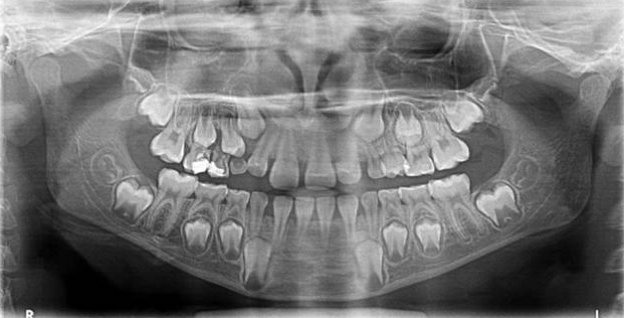

Le cabinet est équipé d’un appareil radiologique KODAK 8000 ceph permettant la réalisation de panoramique et de téléradiographie nécessaires à la réalisation des bilans orthodontiques et au suivi thérapeutique. Ces radiographies numérisées sont de qualité optimale avec des doses minimales d'irradiation.